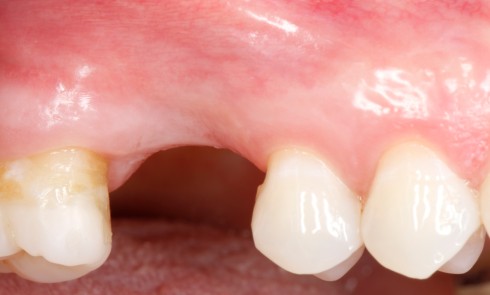

Remaniements tissulaires post-extractionnels L’extraction d’une dent déclenche une série de modifications des tissus environnants [1]. Il existe un affaissement du...